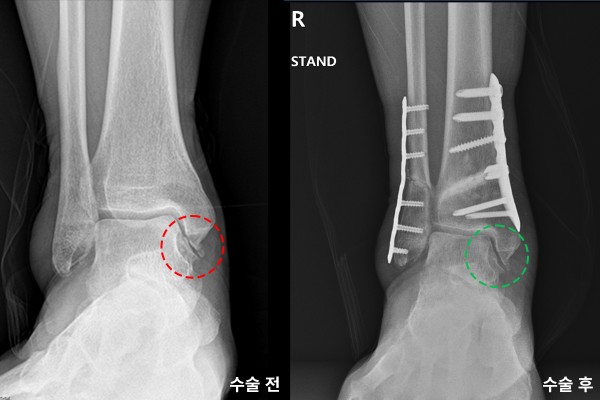

수술 후 X-RAY에서 잘 고정되었고, 발목 안쪽의 공간이 생긴 것이 확인됩니다.

수술 전/후 X-RAY를 비교해보면 더욱 확실하게 알 수 있습니다.